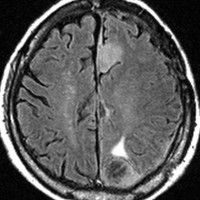

片側髄膜腫症 unilateral meningiomatosis

50歳ころから15年間に3回の開頭手術を受けている患者さんです。parasagittal, falx, convexityなど6個の髄膜腫がすでに摘出されています。左側だけ,テント上だけに髄膜腫が20個くらい多発していました。これらはグレード1で,anaplastic meningiomaの転移ではありません。

初発時から多発性髄膜腫であり,最初の手術で左側テント上の硬膜を広範囲に摘出しておくべきでした。このような病態は若年者でもみられることがあり,胎生期の硬膜の原基になる細胞にmutationが生じたとしか考えづらいものです。